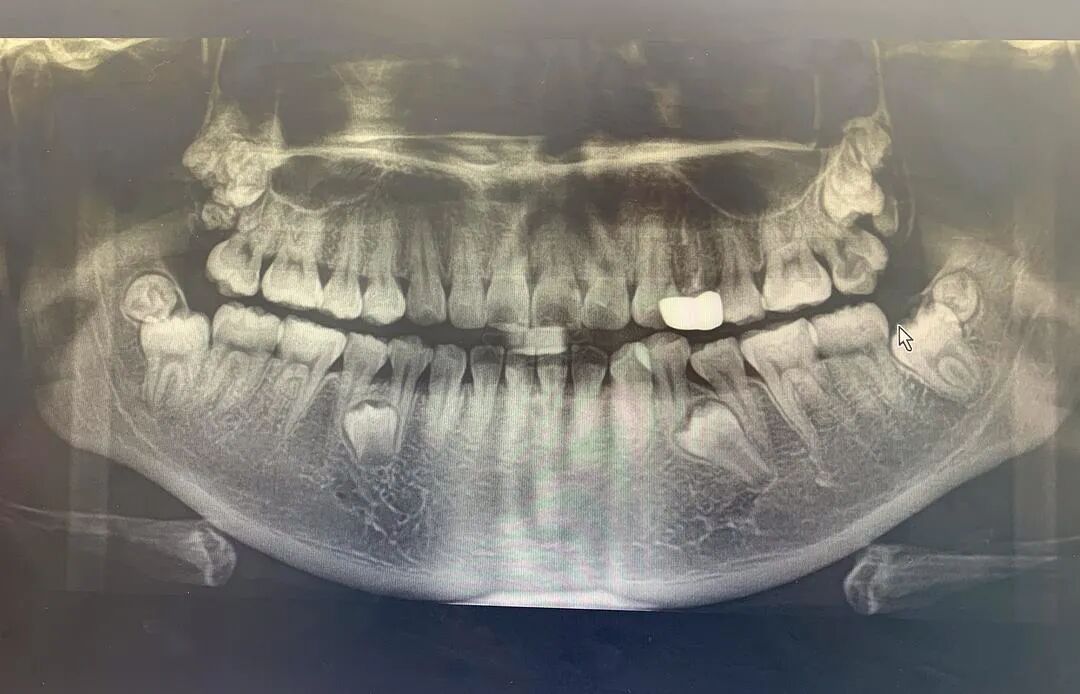

拔除之后

目前除了下面两颗埋伏牙,十二颗智齿全拔除干净了。